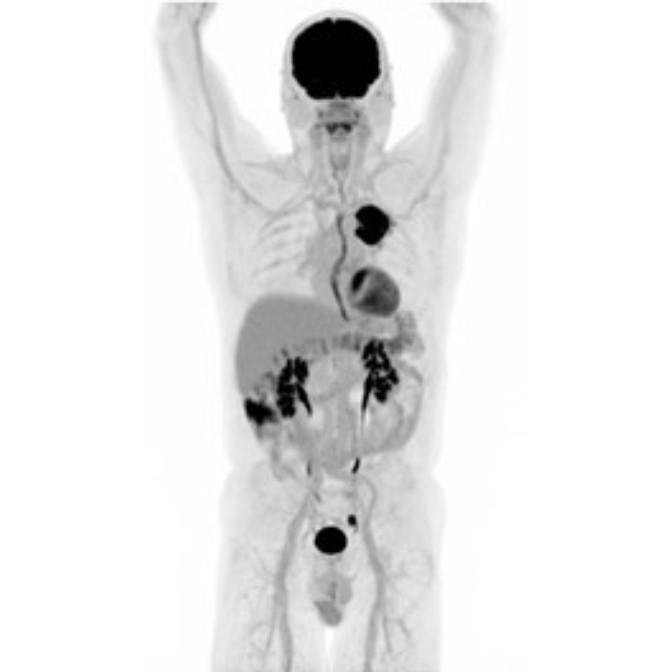

Partial nml and melanoma PET scan

The goal of PET/CT imaging in oncology is to enable the physician to distinguish between benign and malignant pathologies, to determine the extent of disease, to detect residual and recurrent tumors, to monitor the effectiveness of treatments, and to guide therapies.